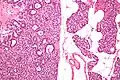

![]() Микропрепарат: слева — аденома паращитовидной железы, справа — неизменённая ткань паращитовидной железы (окраска гематоксилин-эозином). | |

Микропрепарат паращитовидной железы: аденома слева (окраска гематоксилин-эозином).

Паратиреоаденомы из главных клеток образованы крупными полигональными клетками. Цитоплазма их слегка базофильная, мелкозернистая. Ядра крупные полиморфные, встречаются и гигантские, уродливой формы. Строма нежная, обильно васкуляризирована. Критерий наличия аденомы — атрофированная паратиреоидная ткань под капсулой или за ней, а также невозможность обнаружения остальных паращитовидных желез или наличие атрофированных желез. Ультраструктура опухолевых клеток свидетельствует об их высокой функциональной активности и об утрате нормального секрето́рного цикла. В цитоплазме секреторные гранулы и гипертрофированный комплекс Гольджи. Хотя практически во всех клетках выявляется гликоген — нормальные реципрокные взаимоотношения с секреторными гранулами утрачены. В клетках паратиреоаденом в отличие от обычных паратиреоцитов не выявляется цитоплазматический жир[1].

В верхних паращитовидных железах чаще встречаются водянисто-клеточные аденомы, образованные крупными «пустыми» клетками с мелкими гиперхромными яюрами. В них встречаются ацинарные и фолликулярные структуры. Электронная микроскопия выявляет в цитоплазме вакуоли — производные комплекса Гольджи с признаками усиленного синтеза и секреции паратгормона. В физиологических условиях «водянистые» клетки встречаются только у новорожденных[1].

Оксифильно-клеточные паратиреоаденомы — наиболее редкий вариант, встречается при первичном гиперпаратиреозе. По строению они напоминают опухоли из главных клеток, но в них чаще всего формируются крупные со́лидные поля. клетки опухоли богаты митохондриями, характерны признаки синтеза и секреции паратгормона[1].

Паратиреоаденомы чаще всего смешанного строения — образованы всеми тремя типами клеток, однако с преобладанием того или иного типа клеток[1].